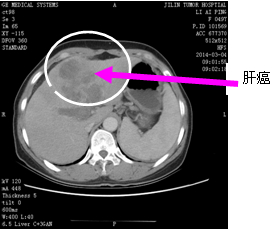

肝膽胰胃外科成功完成肝癌切除同時(shí)門靜脈癌栓取出

肝細(xì)胞肝癌(hepatocellular carcinoma,HCC)是常見(jiàn)的消化道惡性腫瘤之一,在我國(guó)是居于第二位的癌癥殺手。由于肝癌起病隱匿,生長(zhǎng)迅速,發(fā)現(xiàn)時(shí)往往已近晚期,且其中有相當(dāng)比例的患者伴有肝細(xì)胞癌侵及門靜脈主干或第一級(jí)分支形成門靜脈癌栓(portal vein tumor thrombi,PVTT),常被認(rèn)為不宜行手術(shù)治療,既往對(duì)其多采用消極的方法或放棄治療,大多數(shù)患者在數(shù)月內(nèi)死亡,同時(shí),PVTT的出現(xiàn)表明肝癌已近中晚期,也是引起患者門靜脈高壓、肝功能惡化、肝內(nèi)廣泛轉(zhuǎn)移及術(shù)后復(fù)發(fā),進(jìn)而影響療效及預(yù)后很差的主要因素。隨著對(duì)門靜脈癌栓認(rèn)識(shí)的深入和手術(shù)技術(shù)的改進(jìn),肝癌伴門靜脈癌栓患者臨床療效有了較大幅度的提高。

肝膽胰胃外科采用的方法為行肝切除后,控制門靜脈主干,開(kāi)放肝切面上門靜脈殘端,用鋏鉗或吸引器頭插入門靜脈腔內(nèi)將癌栓吸出,或用導(dǎo)管插入以生理鹽水沖吸。門靜脈阻斷放松后見(jiàn)殘端血流噴出呈扇形,提示癌栓已被除去,縫合門靜脈殘端。術(shù)畢用彩超即時(shí)檢測(cè)門靜脈主干及分支,觀察癌栓是否已完全清除干凈。通過(guò)CT復(fù)查門靜脈主干及分支血供情況。文獻(xiàn)顯示應(yīng)用此法,患者術(shù)后半年、1年和2年生存率為95.4%,47.0%和20.0%。但在實(shí)際操作中,應(yīng)用此方法有時(shí)難以將癌栓清除干凈,殘留癌栓或微小栓子肝內(nèi)播散而導(dǎo)致復(fù)發(fā),遠(yuǎn)期療效并不理想。隨著外科技術(shù)的不斷完善,對(duì)于PVTT認(rèn)識(shí)的逐步深入,將會(huì)有越來(lái)越多的肝癌合并PVTT患者接受外科手術(shù)治療。肝膽胰胃外科通過(guò)術(shù)前充分的肝臟功能及肝臟儲(chǔ)備功能檢查,確定該患者可以接受此手術(shù)方案,并成功實(shí)施了手術(shù),目前患者已經(jīng)康復(fù)出院。肝膽胰胃外科肝癌切除同時(shí)取出門靜脈癌栓是一種有效的治療方法,為PVTT的根治性切除、防止早期肝癌復(fù)發(fā)做了一個(gè)有益的嘗試。